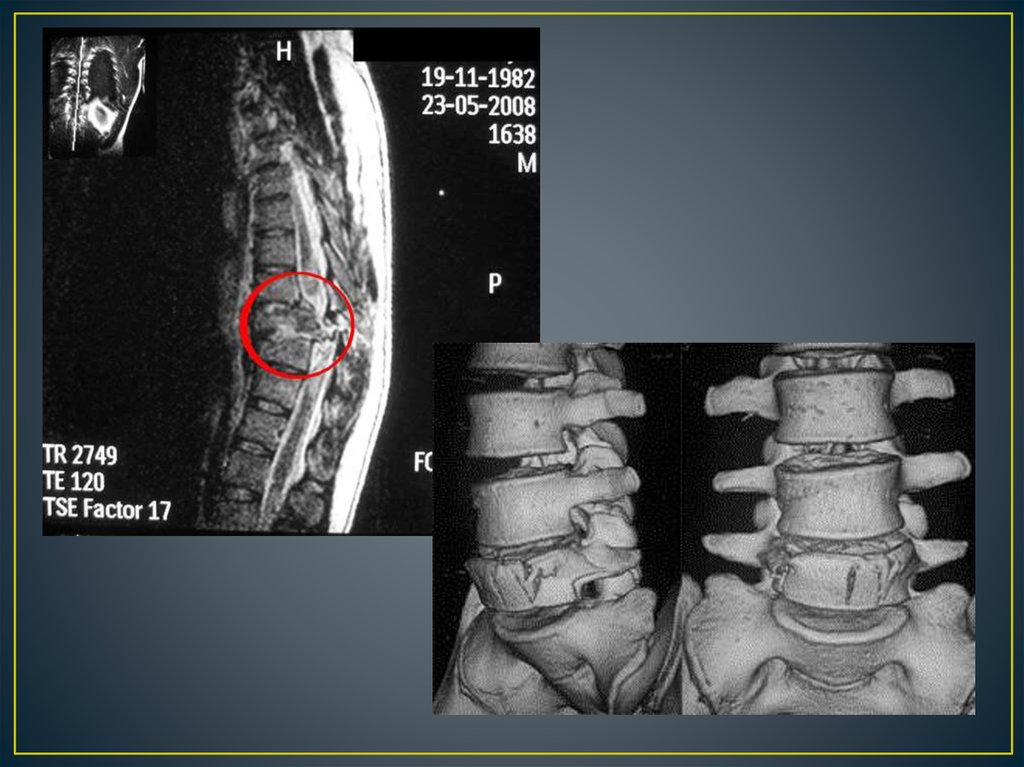

Позвоночно – спинальная травма